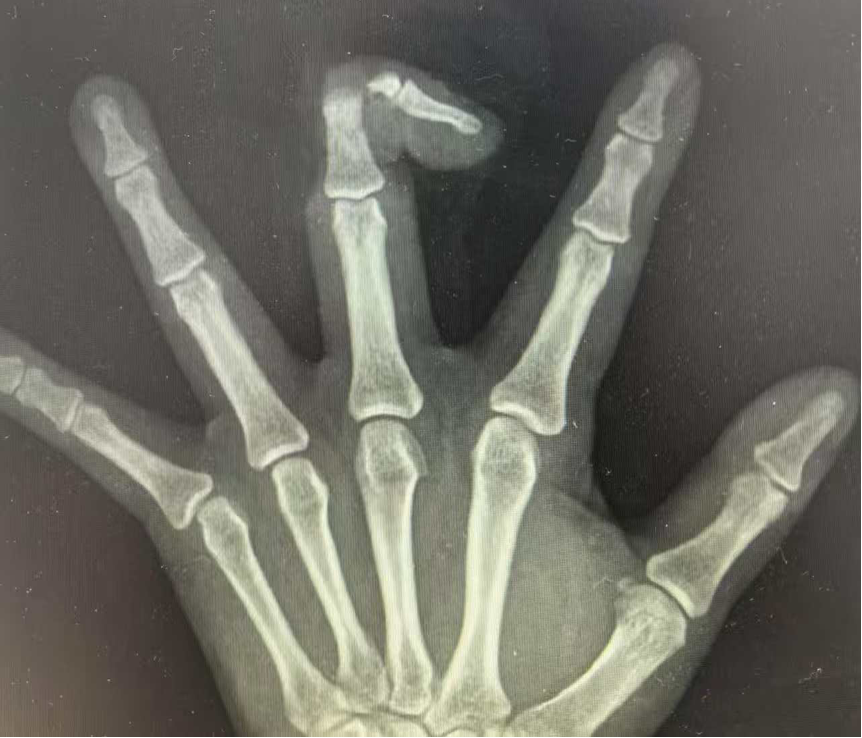

近日,张先生(化名)不慎被机器绞伤手指,导致他右手中指自中节指骨处完全离断,张先生紧急前往我院急诊医学科,到院时,他的伤口疼痛剧烈,断指残端出血不止,离断的指体苍白没有血运,情况非常危急。

张先生断指影像

急诊医学科立即启动创伤急救绿色通道,并联系手足显微外科团队进行会诊。专家团队会诊后认为,患者是挤压伤导致的完全性断指,断面平整,但是血管神经束清晰,具备断指再植的条件,可以立即进行手术!

在麻醉科、手术室的通力配合下,手足显微外科团队为张先生争分夺秒地开展了再植手术。术中,医生们在显微镜下精细清创,依次完成骨折固定、肌腱缝合、指动脉吻合(0.3mm血管)、指神经修复以及静脉吻合等高难度操作。